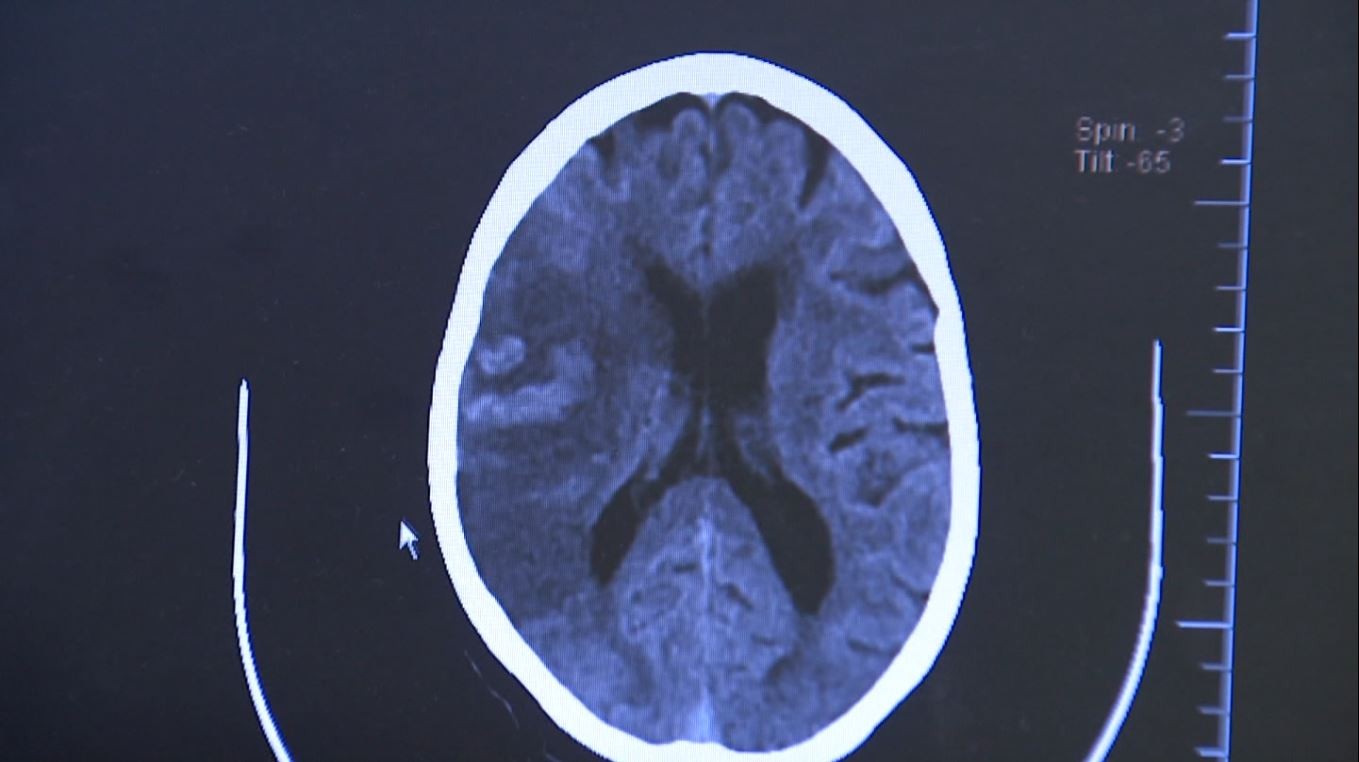

webradio016 Atendimentos de casos de AVC saltam 127% na região de Campinas em 5 anos

Em 2020, foram realizados 15.357 atendimentos no DRS de Campinas, número que chegou a 34.970 em 2024. Atendimentos para casos de AVC saltaram 127% na região de Campinas em 5 anos O número de atendimentos por Acidente Vascular Cerebral (AVC) aumentaram 127% em 5 anos na região de Campinas (SP). Em 2020, foram realizados 15.357 atendimentos no Departamento Regional de Saúde (DRS) de Campinas, número que saltou para 34.970 em 2024. O cardiologista Bruno Colontone explica que qualquer pessoa pode ter um AVC, mas fatores de risco como hipertensão e diabetes aumentam as chances. Familiares e ex-pacientes relatam as dificuldades enfrentadas após sofrerem um derrame. Siga o g1 Campinas no Instagram 📱 Em 2022, Sara Barbosa teve um AVC de tronco, conhecido como síndrome do encarceramento, quando a pessoa permanece lúcida, mas perde a fala e os movimentos do corpo. Ela tinha 36 anos e ficou internada por 180 dias. "Foi um processo muito difícil, ela teve muitas infecções, tomou muito antibiótico, ela teve dois TEP [tromboembolismo pulmonar]. Foi um processo muito doloroso, muito difícil. A gente achou que ia perder a Sara", conta Sabrina Barbosa, irmã e cuidadora de Sara. Depois do AVC, Sabrina conta que a rotina e os cuidados mudaram. A medicação e a alimentação são feitas por sonda. A dieta enteral precisa ser administrada três vezes ao dia. "Tudo é feito no leito. E a nossa comunicação veio pelo olhar, tudo que é positivo ela olha para cima e negativo para baixo" Seu Antônio Adelino de Souza, de 67 anos, sofreu um AVC há quatro meses, enquanto estava internado no Hospital Mário Gatti para tratar uma infecção no braço. Hoje, ele se recupera em uma clínica. "Eu levanto, eu me esforço em caminhar um pouquinho, me esforço em fazer exercícios, fazer oficina de terapia física e devagarzinho a gente 'vai indo', né? Porque, se você se entregar, você fica na cama direto. Graças a Deus, estou bem melhor do que estava antes", conta seu Antônio. Atendimentos na região Em 2020, o número de atendimentos por AVC foi de 15.357 na DRS Campinas. O número saltou para 34. 970 em 2024, o que representa um aumento de 127%. Ou seja, os casos mais que dobraram na região. Em 2025, entre os meses de janeiro e março, já foram 7.673 atendimentos por AVC realizados na região. 2020 - 15.357 2021 - 26.169 2022 - 32.524 2023 - 33.524 2024 - 34. 970 2025 - 7.673 (janeiro a março) Segundo o cardiologista Bruno Colontone, qualquer pessoa pode ter um AVC, mas fatores de risco aumentam as chances. "A hipertensão arterial está muito correlacionada com o AVC. Diabetes, alterações de colesterol, aumento da gordura abdominal, gordura no fígado, estresse, sedentarismo, obesidade, todos esses são fatores que aumentam a chance da pessoa ter AVC", afirma. Colontone explica que o AVC é uma doença que afeta os vasos sanguíneos no cérebro e que está correlacionada com a falta de irrigação de oxigênio para os neurônios. "Isso acontece por dois mecanismos. Ou um entupimento, ou seja, a gente chama de isquêmico, quando forma um coágulo que entope o fluxo de sangue, ou quando você tem uma ruptura de um desses vasos, que seria o hemorrágico", explica o cardiologista. Atendimentos para casos de AVC saltaram 127% na região de Campinas em 5 anos Reprodução EPTV VÍDEOS: saiba tudo sobre Campinas e região Veja mais notícias sobre a região na página do g1 Campinas. Fonte: G1